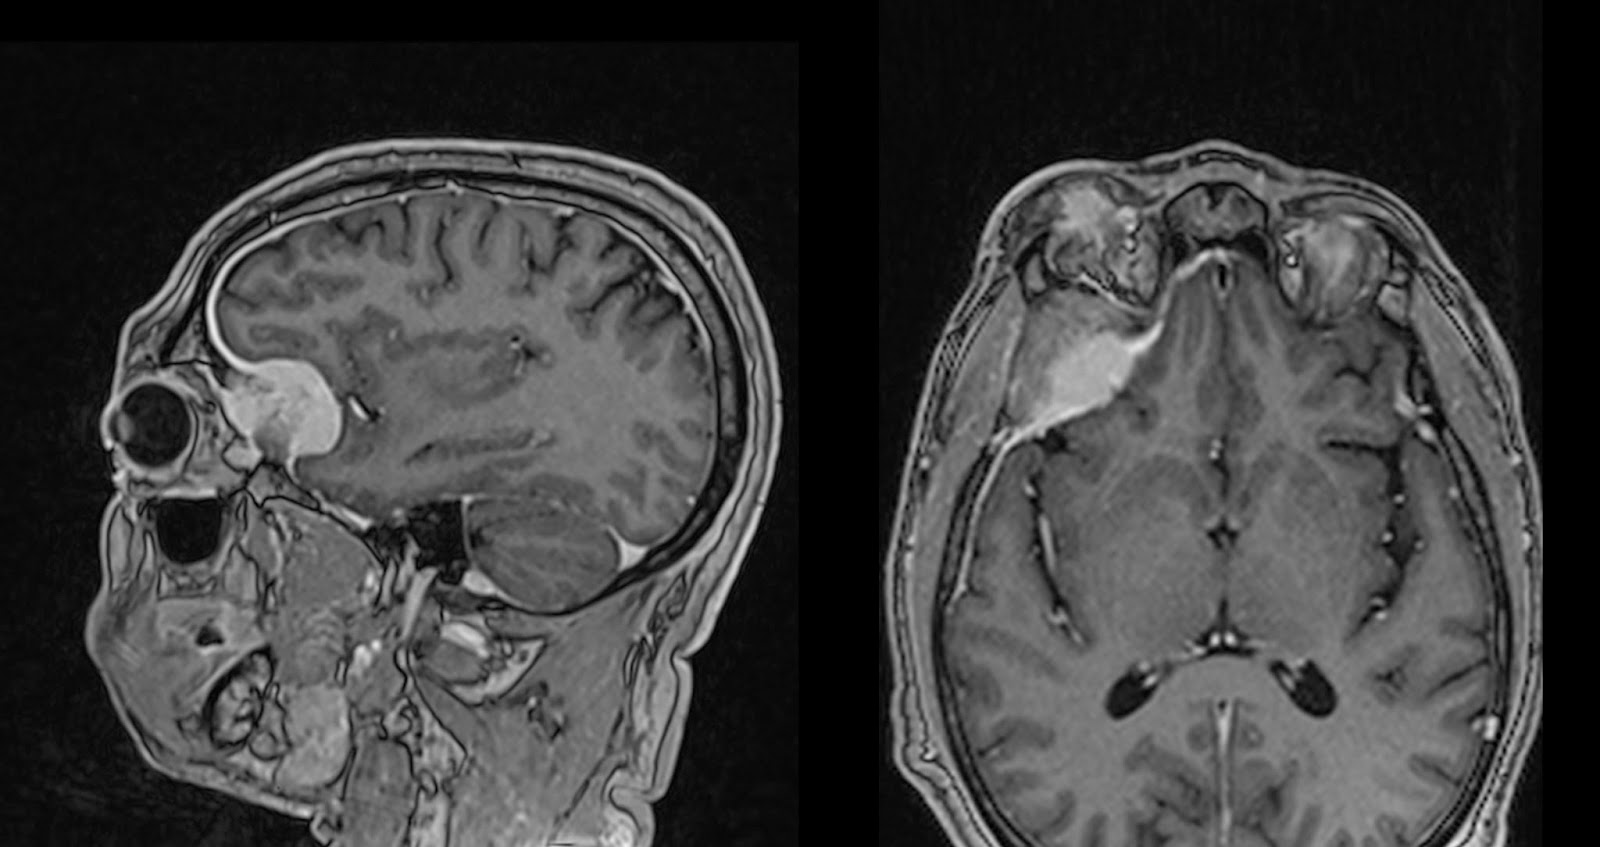

Последствие менингиома

Последствие менингиома 114 фотографий